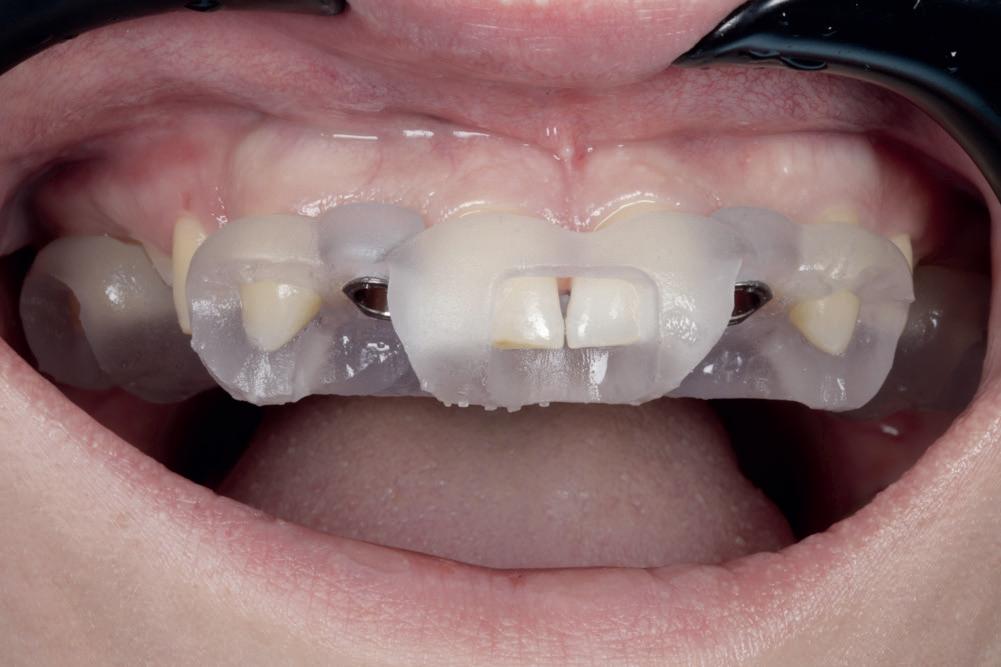

CASE STUDY

Guided implant approach for reproducible results, page 28

1. Adaptable to different guided surgery protocols: piloted, semi-guided or fully guided.

2. No friction between drills and guide sleeve, no overheating and no release of particles.

3. No specific drills and a very small surgical box.

4. Full control of drilling depth.

5. Your conventional driver-guided drilling sequence.